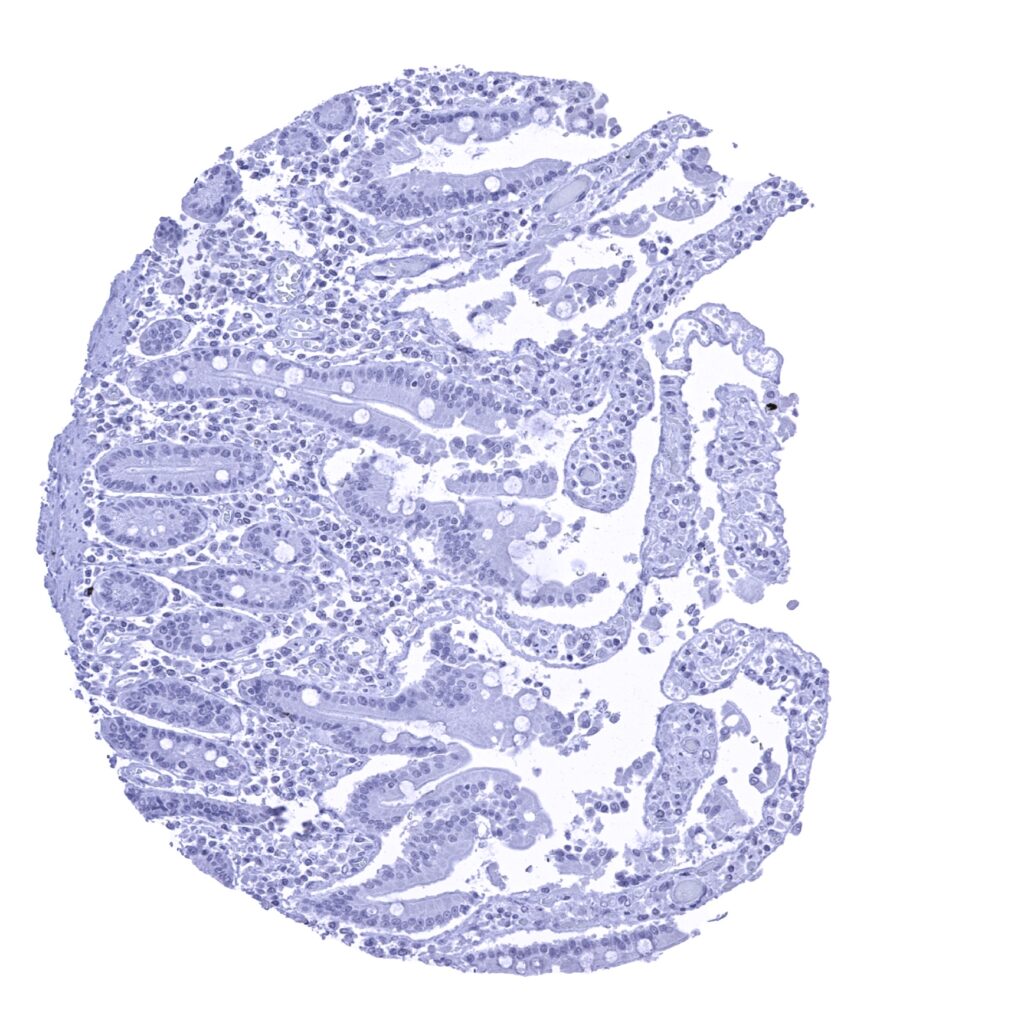

Ileum, mucosa